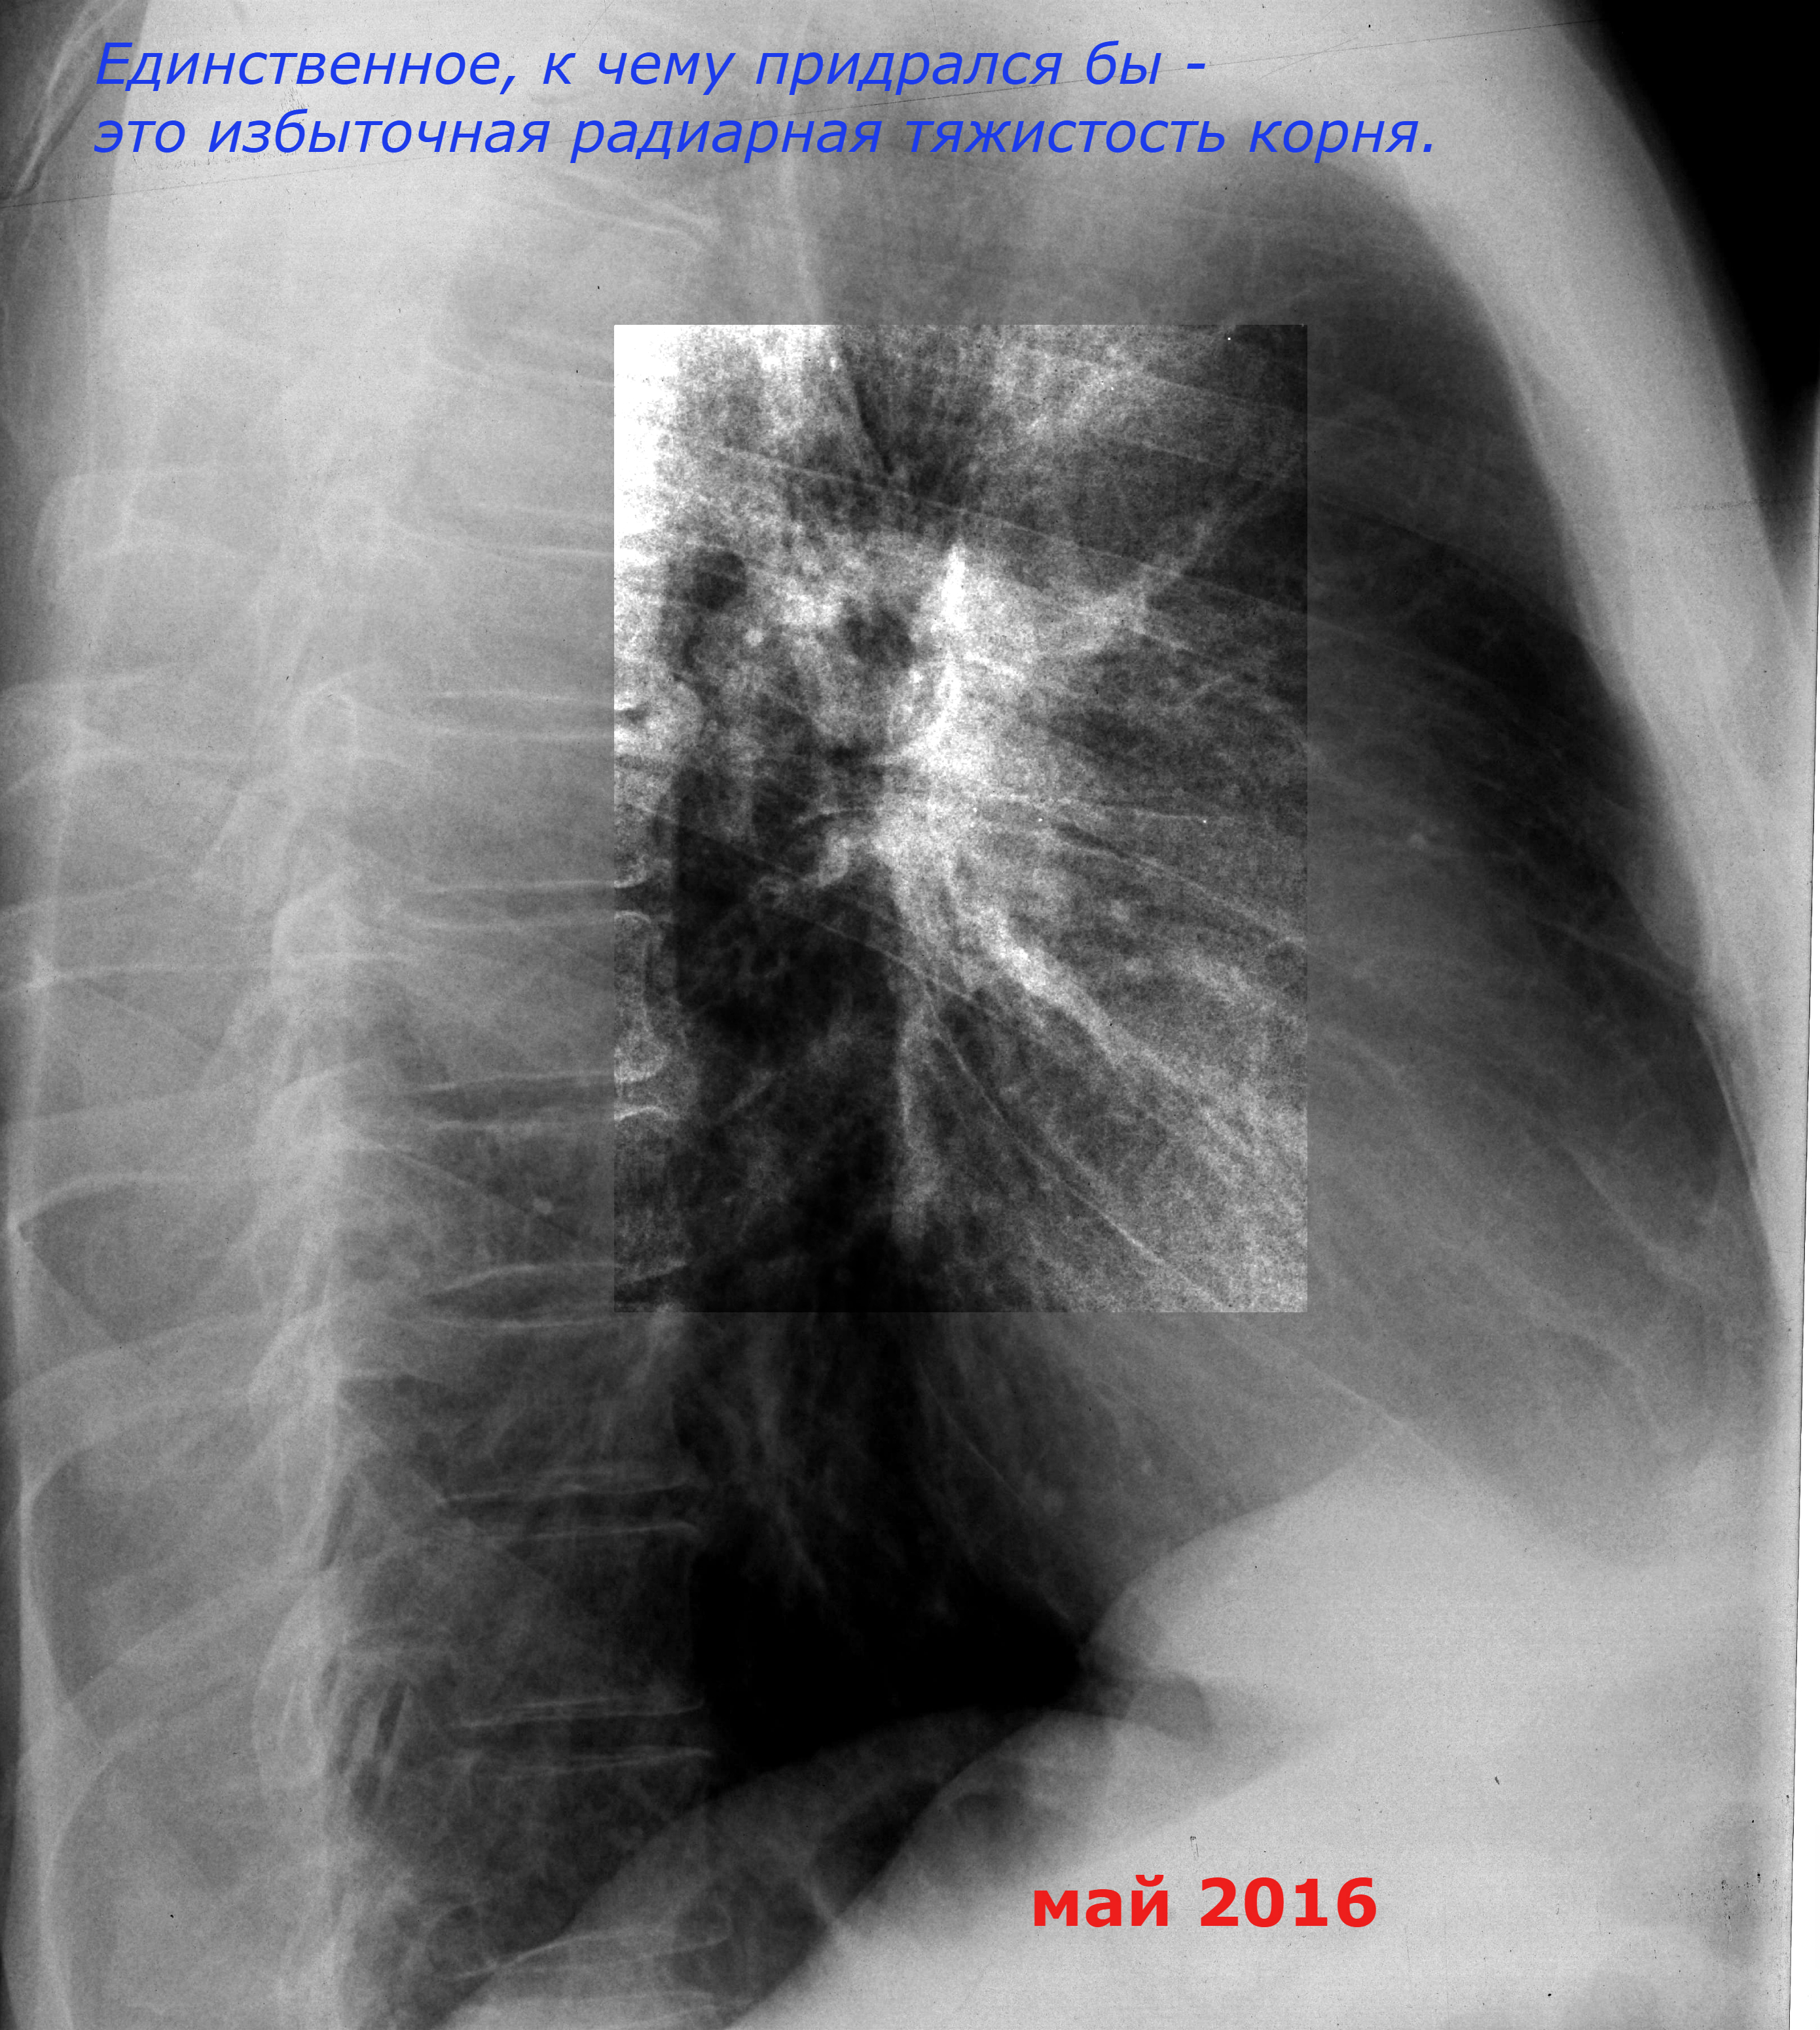

Муж. 1946гр. в мае 2016г выявлен центральный рак. Рентген от 21.09. и май 16г.

Положа руку на сердце, я бы тоже. Но при втором-то снимке есть и боковой! Посмотрите какой "тяжик" странный на обоих появился, а корень каков? Потом ведь клиника-то сразу - кровохарканье, возраст опять же! Амбулаторную карту/ историю болезни читаем! Ведь не зря же существует порядок обязательного дообследования при кровохарканье, смотря, конечно, чем оснащена больница: минимум-тмг ч/корни, максимум-КТ. Так что всё сделали правильно наши коллеги.

Наконец-то, поставили вместе два обзорных снимка в динамике (правда, не в том порядке, но не беда). К сожалению, сам не смог по тех.причинам. Внимательно посмотрите на корень правого легкого на сентябрьском снимке. По сравнению с майским, отрицательная динамика: расширение и потеря дифференцировки, преимущественно в области хвоста корня ("Признаками узла в корне легкого являются потеря структурности и увеличение интенсивности тени корня, расширение его границ кнаружи"). А так же усиление, сгущение легочного рисунка в медио-базальном отделе правого легкого (гиповентиляция). Можно не говорить об онкологии (хотя возраст пациента, кровохарканье должны настораживать), но и отмечать в заключении норму не совсем профессионально. А дальше, дообследовать; потому что мы врачи-рентгенологи, т.е. специалисты (два в одном!), а не просто, клиницисты.